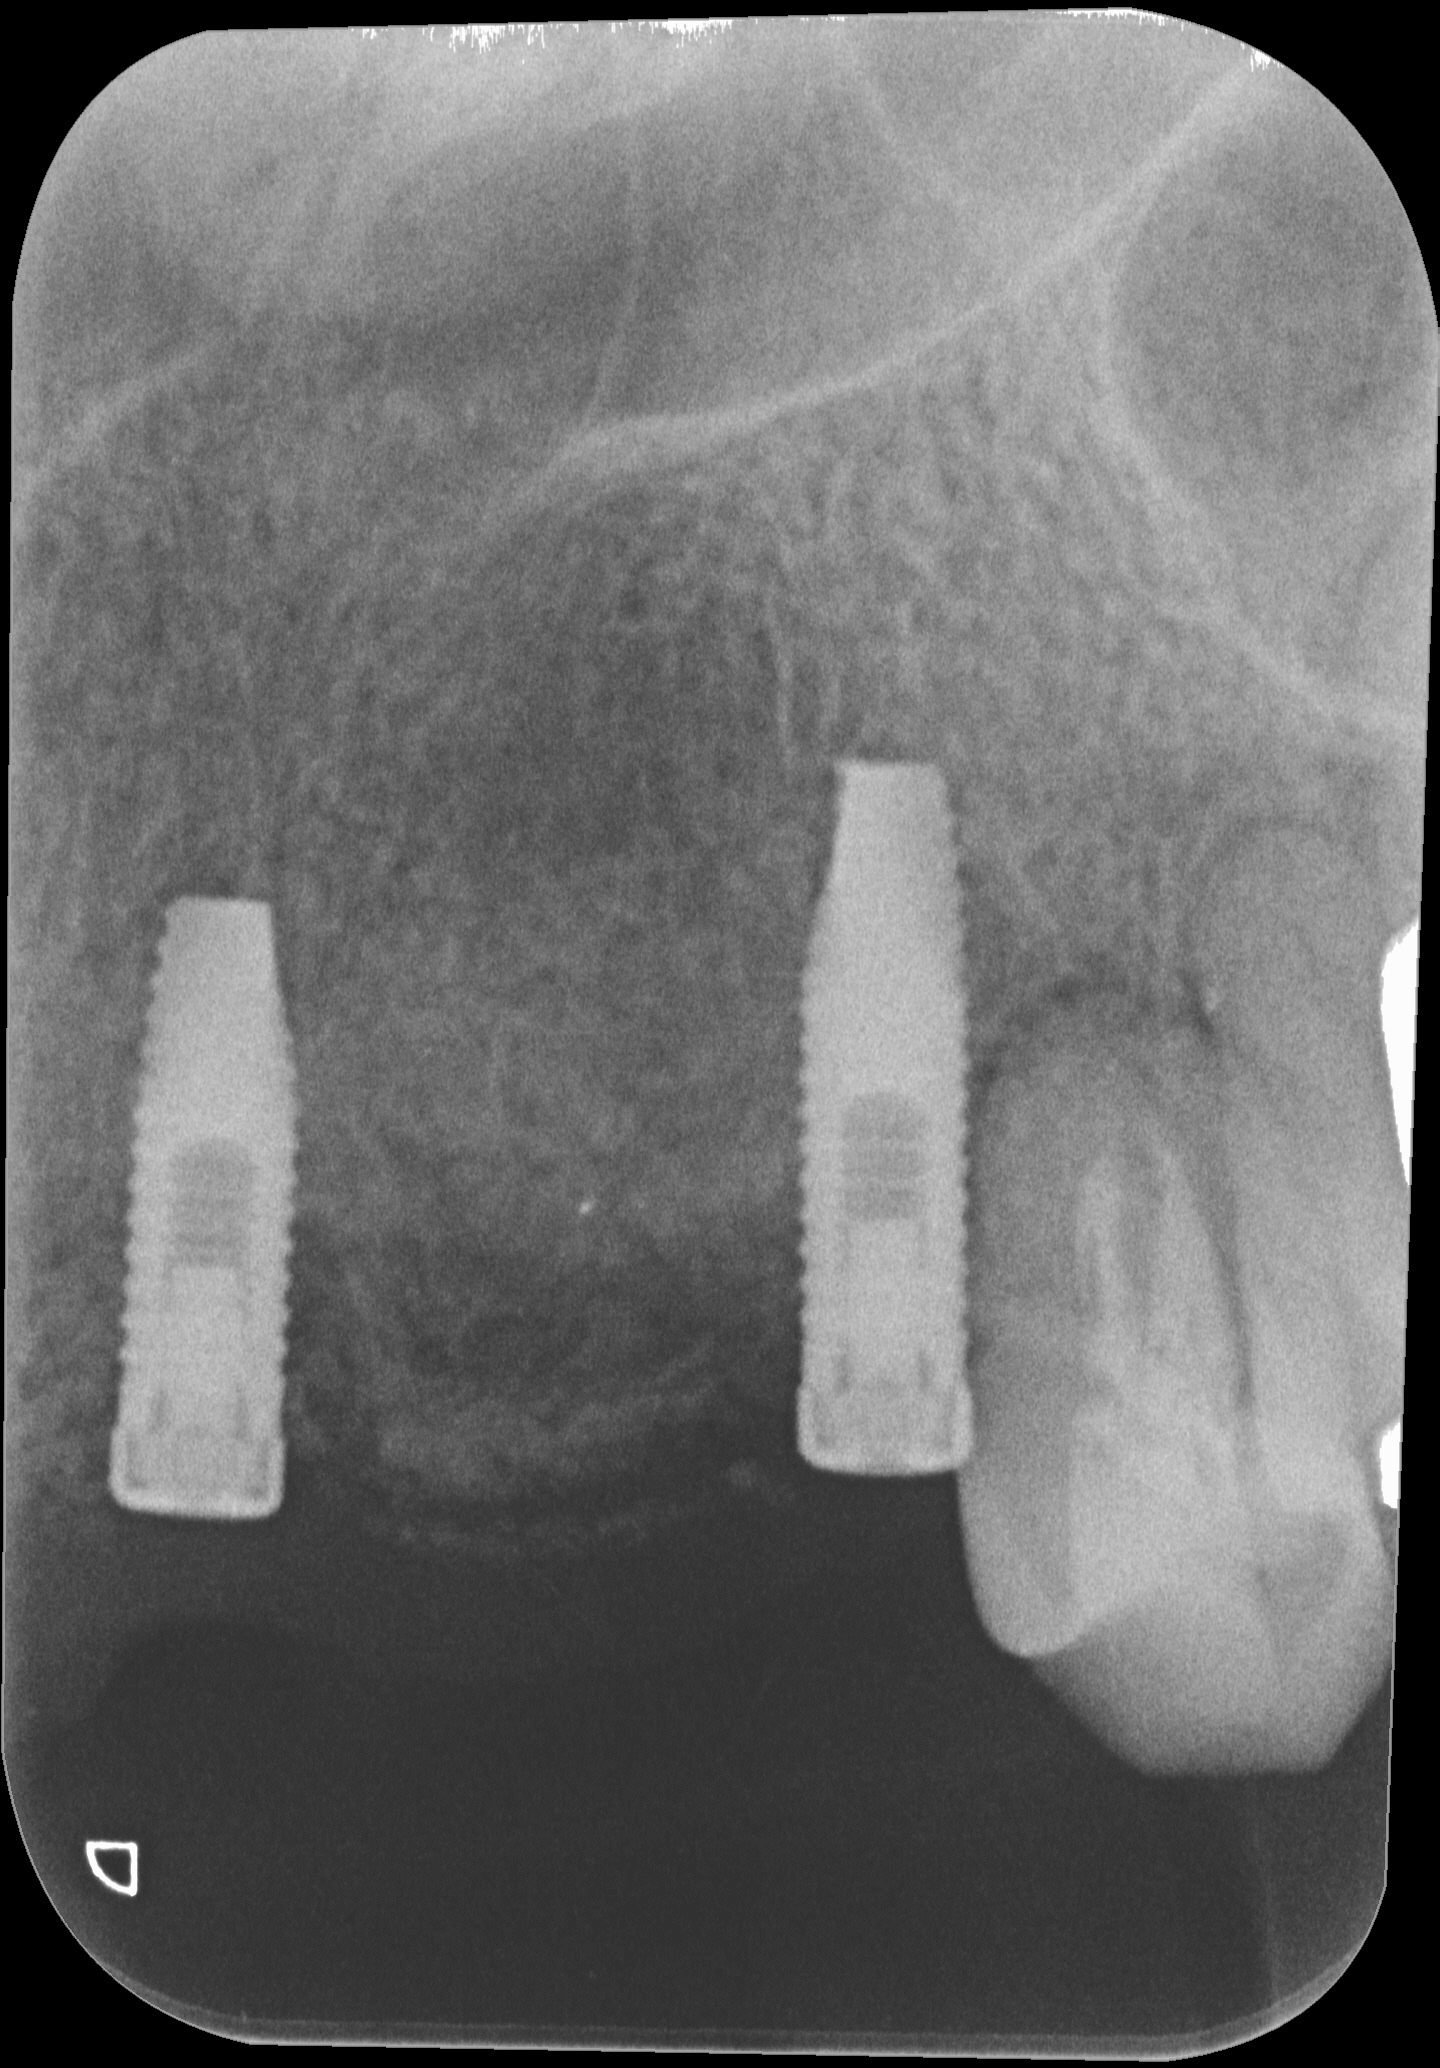

埋入後のレントゲンですが、完全に平行に入っていますが、これも大事です。